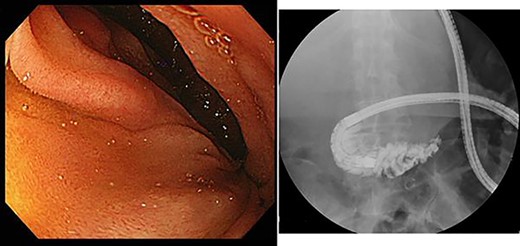

However, during hospitalization, the patient developed dehydration, acute renal failure, electrolyte imbalance and impaired consciousness. C-reactive protein level was elevated (9.61 mg/dL), indicating intracystic infection. As emergency treatment, percutaneous puncture drainage of the cyst was performed to decompress the stomach and duodenum (Fig. 4).

Percutaneous puncture drainage improved the obstruction of duodenum.

A total of 1400 mL of purulent fluid was drained, and cytology of the drainage fluid showed no malignant findings. The gastrointestinal obstruction symptoms improved, enabling oral food intake; thus, we decided to perform laparoscopic deroofing of the hepatic cyst.